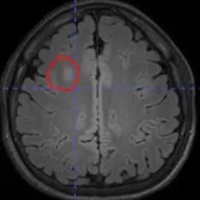

脑电图检查提示:右侧额叶异常放电。但常规头颅磁共振检查,始终未能发现明确的致痫病灶。面对这种情况,只能先通过药物控制病情。

借助医院先进的高清晰度、高对比度薄层扫描核磁共振,配合PET-CT检查,终于在右额叶发现了一个极其微小的致痫病灶。这个位置,与脑电图提示、以及临床发作特征完美吻合。更幸运的是,虽然病灶位置深,但范围很小。

经过详细的术前评估,神经外科二病区李培栋主任和李信晓博士团队设定了精密的手术方案,精准植入了6根颅内电极,刚好将病灶完整包围。

在接下来的几天里,通过电极直接记录到了发作期异常放电的源头,进一步验证了它就是真正的“元凶”。更关键的是,电极的覆盖范围足够精密,明确了病灶边界,且避开了重要的功能区——这意味着,我们不仅能抓住它,还能就地解决它。

有了SEEG提供的精确“地图”,随即通过电极对这块仅几立方毫米的脑组织进行了“射频热凝毁损”。